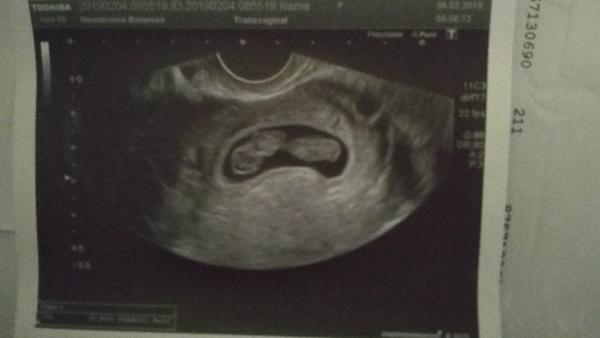

Tak co, máte "dvě čárky"? - termín porodu v září 2019

Krásný!! Já už chci taky ultrazvuk, holky jsem dojatá.. ty hormony 😀